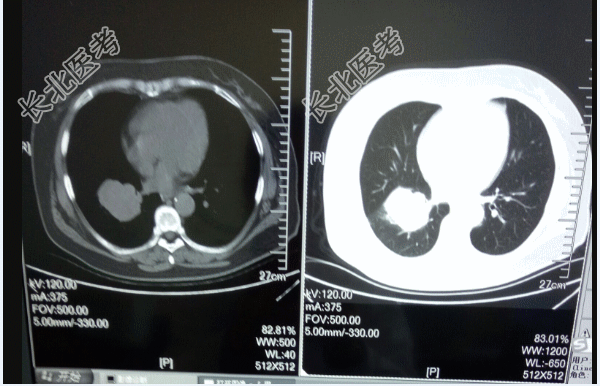

- [材料题] 女性,53岁,农民。右肺小细胞肺癌1月余。现病史:患者于3个月前无明显诱因出现咳嗽,咳痰症状,伴气短,无夜间阵发性呼吸困难,活动后加重,无胸痛,无咳血,无午后低热,盗汗,口服消炎药物,症状无改善。出现喘憋、呼吸困难,不能平卧,肺CT示右下肺门占位伴周围炎症,肺癌可能性大,右肺下叶背段及左肺上叶多发小结节病变。气管镜检病理及免疫组化:P63(-),P40(-),CGA(-),SYN(-),NSE(-),CD56(+),TTF-1(+),ALK(-),EGFR(-),MAP2(+),ki67(80%).LCA(-),符合小细胞肺癌,为化疗入院。病来咳嗽咳白痰,喘憋,活动加重,无咯血,无明显胸痛,无头痛恶心呕吐,食欲可,二便正常,夜睡眠欠佳。

辅助检查:肺CT:右下肺门占位伴周围炎症,右肺下叶背段及左肺上叶多发小结节病变。彩超、CT未见远处转移。血尿常规,肝肾功能、血凝、心电图等相关检查无化疗禁忌。